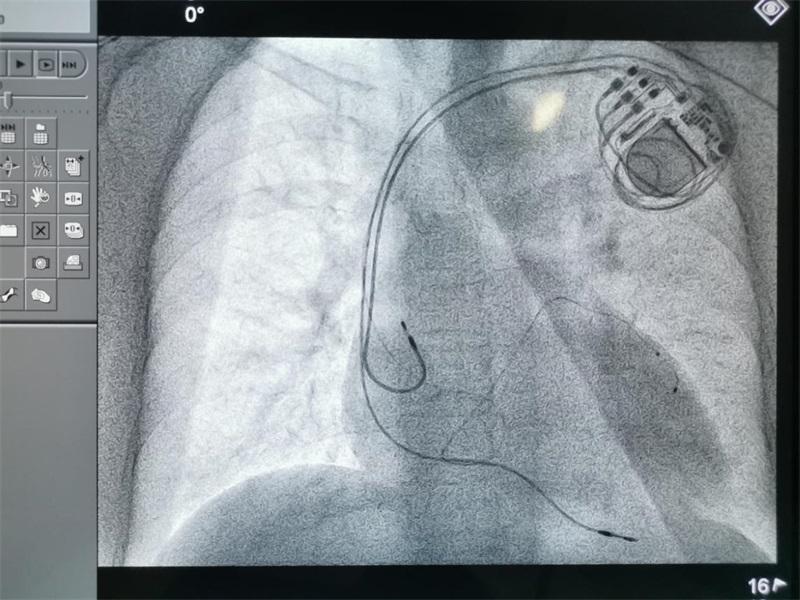

9月8日,南昌大學一附院心內科團隊為一名高危心力衰竭患者完成3D打印心臟模型指導下心臟再同步化治療(Cardiac Resynchronization Therapy,CRT)植入術。手術由王夢洪教授、彭景添教授、彭小平教授共同完成,該手術的成功開展,標志著該院院心內科治療技術再上新臺階。

術前,彭小平教授積極與影像科聯系、溝通,根據患者心臟CT圖像三維重建,通過3D打印技術,立體展示冠狀靜脈各分支以及心腔的空間結構,重建帶有冠狀靜脈分支的心臟立體模型,精確指導左、右心室電極、心房電極植入位置。手術過程中,術者在3D打印心臟模型精準指導下,將左室冠狀竇電極精準定位于冠狀靜脈左室外膜面分支,右室螺旋電極及心房電極分別定位于右室心尖部及右心耳,最后連接起搏脈沖發射器。因有了3D打印心臟模型的指導,手術較平時手術較少了近30分鐘。